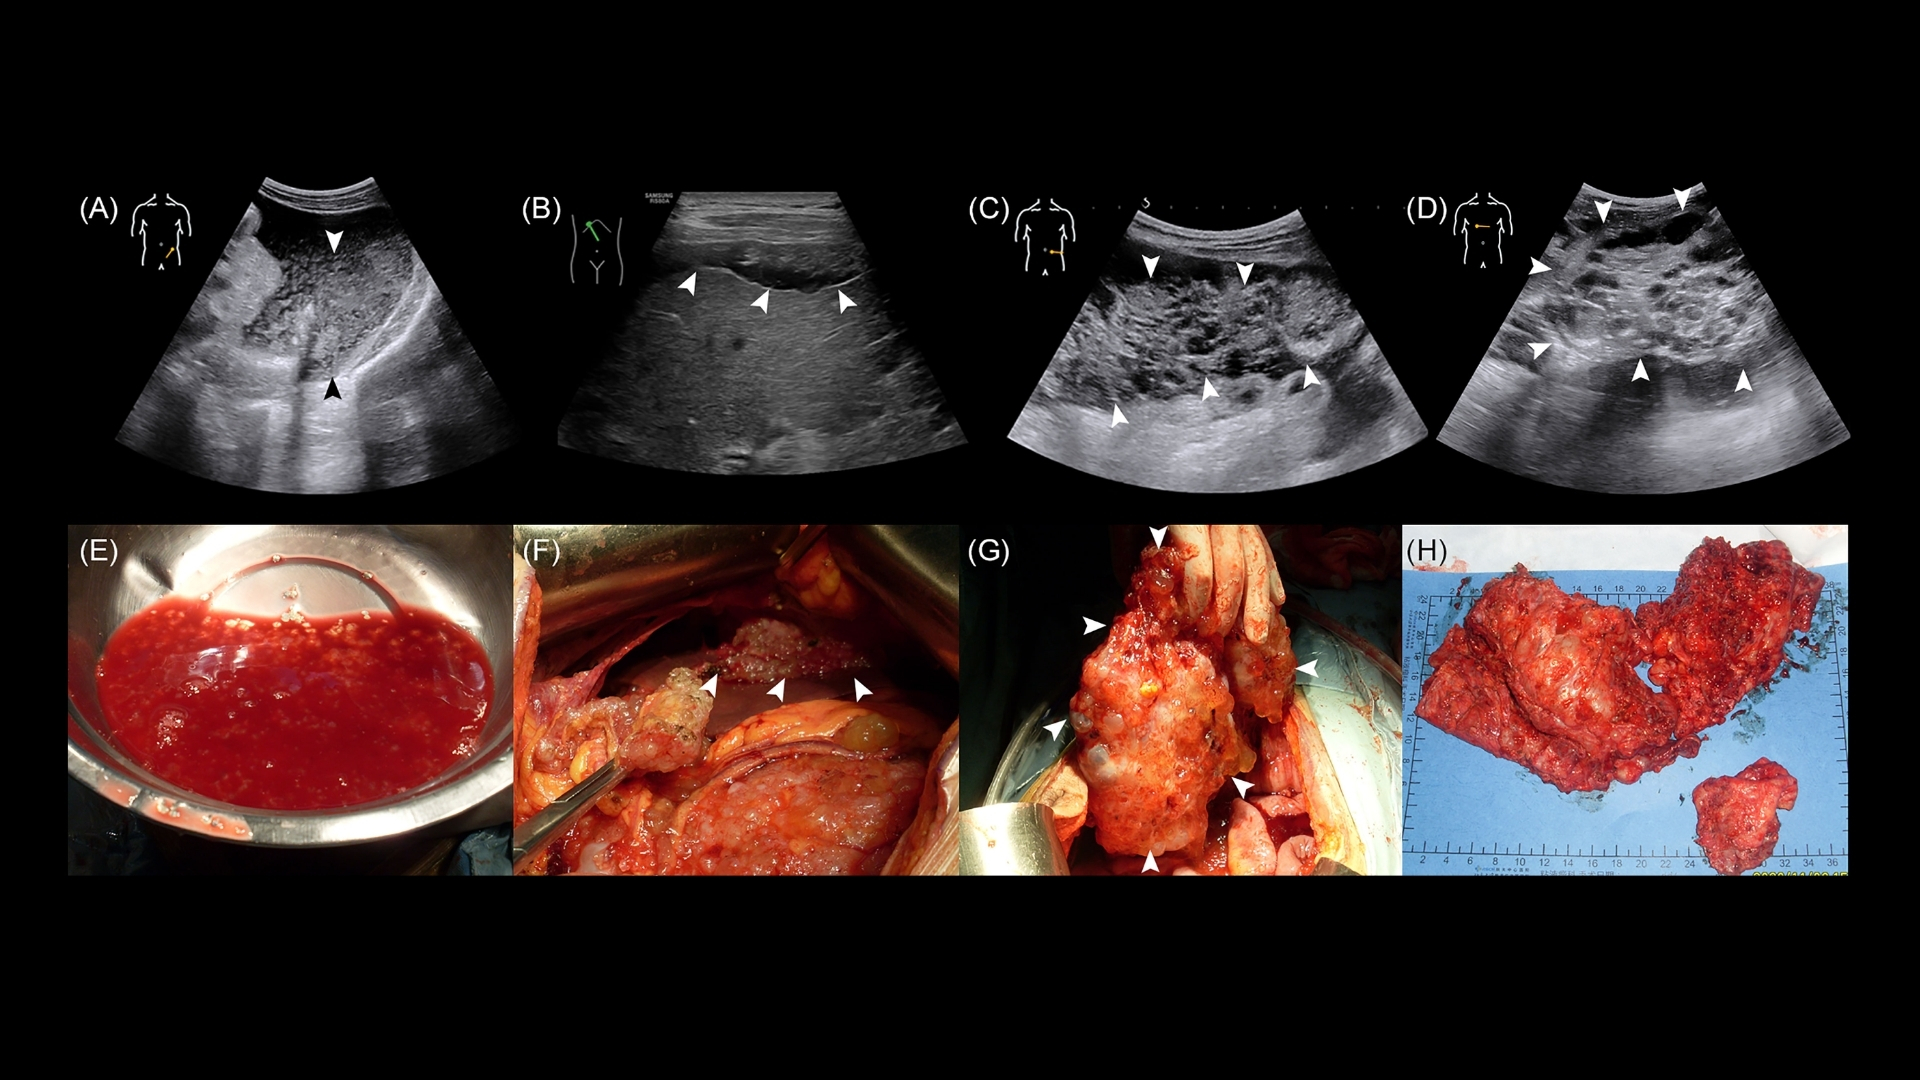

假性腹膜肌瘤 (PMP) 診斷 涉及多方面的方法,以準確評估該疾病的程度和性質。診斷方法很全面,包括:

• 活檢: 核心針切活檢是常見的方法。對於 PMP,細胞切除手術可對組織進行病理檢查,確保診斷的準確性。

• 成像技術: PET-CT 和 MRI 掃描可提供腫瘤生長及其對周圍器官影響的詳細影像。這些方法對於分期、判定 PMP 的擴散性和侵襲性至關重要。

• 手術: PMP 治療的基石是細胞復原手術結合腹腔內熱療化學治療 (HIPEC)。這種積極的方法旨在盡可能移除腫瘤塊,並直接在腹腔內使用加熱化療針對殘留的癌細胞。